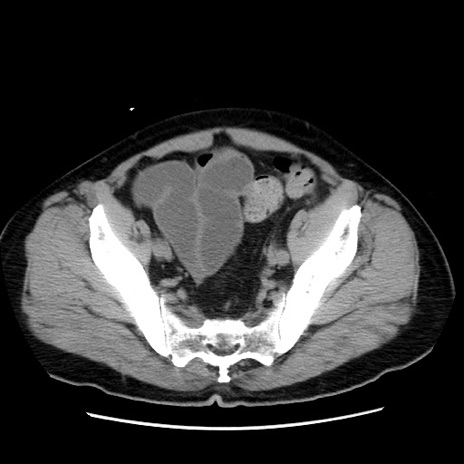

症例16(横断像)

【症例】 70歳代男性

【主訴】 腹痛、嘔吐

【現病歴】 約1ヶ月前より間欠的に腹痛と嘔吐あり、当院消化器内科を受診したところCTで多発する肝臓のLDAを指摘され、精査中であった。以降は消化器症状は安定していたが、2日前より嘔気と腹痛があり、同日より排便・排ガスが消失した。改善認めず、 本日、救急外来を受診した。

【身体所見】意識清明・会話良好、BT 36.3℃、BP 127/80mmHg、 P 80bpm、腹部:膨満あり、平坦・軟、上腹部正中および下腹部正中に圧痛あり、反跳痛なし、筋性防御なし。

【データ】WBC 7200、CRP 0.77